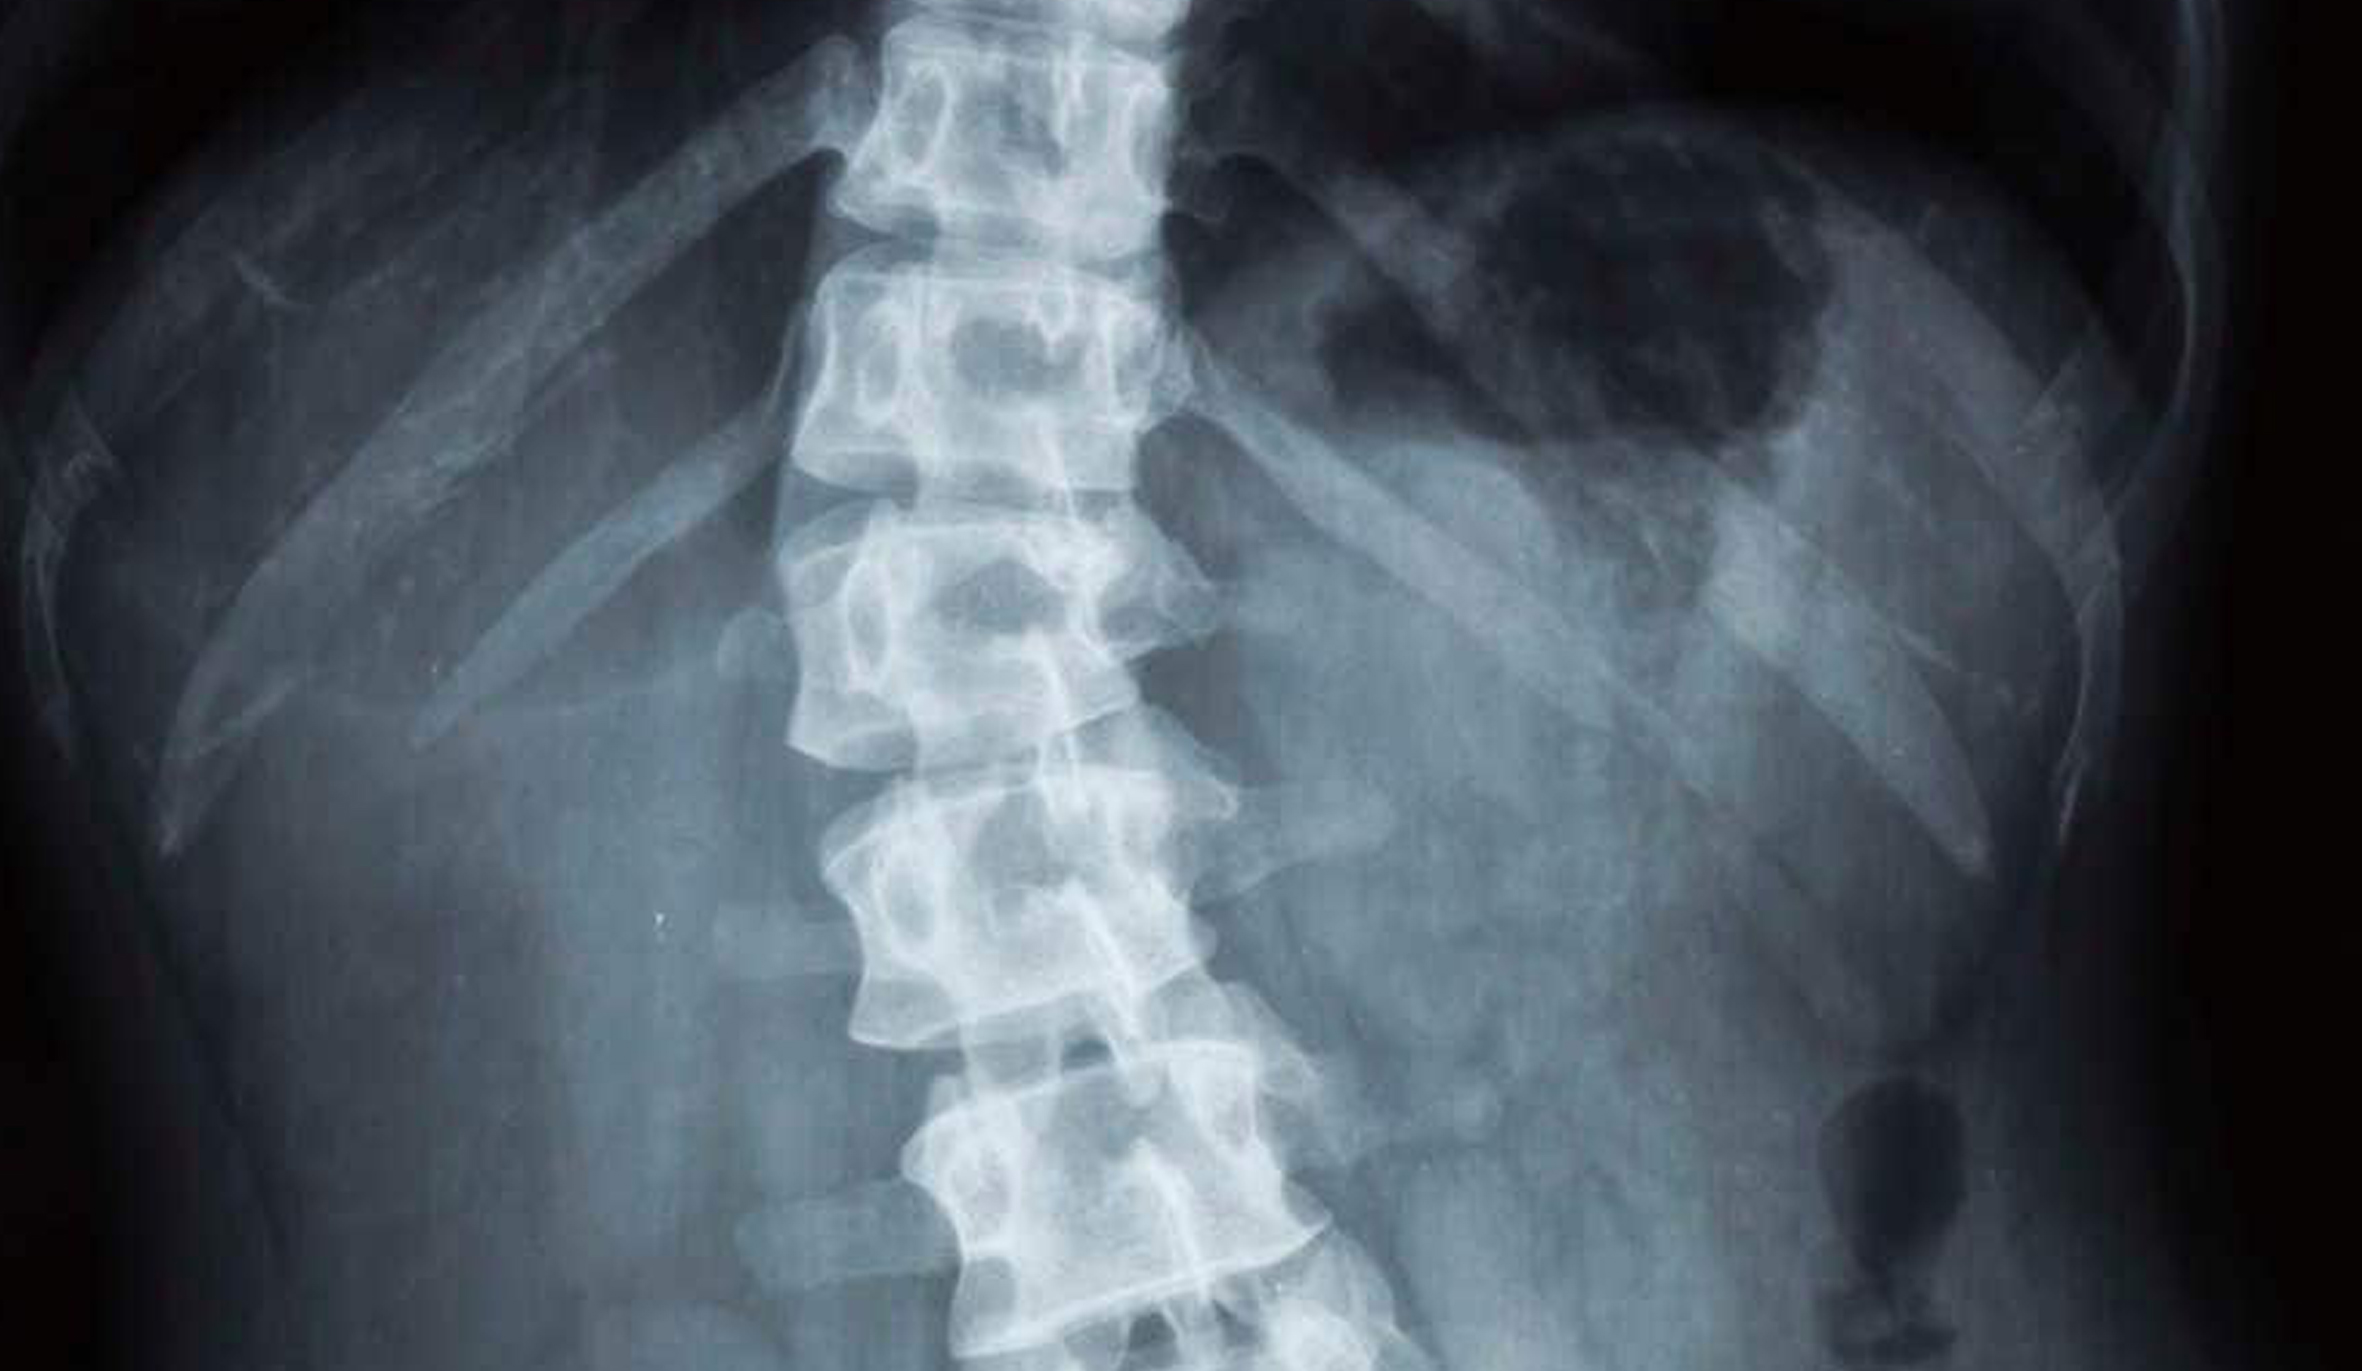

Traumi vertebrali (fratture da osteoporosi e traumatiche).

Deformità della colonna vertebrale (scoliosi, cifosi, spondiololistesi).

Patologie degenerative della colonna (ernia del disco; discopatia degenerativa, stenosi del canale vertebrale, scoliosi degenerativa dell’adulto).